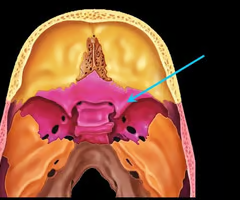

Sella turcica (holds pituitary gland - “Turk’s saddle”)

Cribriform plate of the ethmoid bone (notice olfactory formina in it - for olfactory nerves. Crista galli “rooster’s comb” dura mater attaches here)

Perpendicular plate of the ethmoid bone (helps form bony nasal septum with vomer)

Optic canals (optic nerve)

Optic canals (optic nerve)